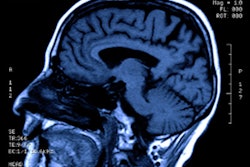

MRI shows that the sex of a concussed child has bearing on how their symptoms manifest -- findings that could help clinicians better tailor treatment, according to research presented at the recent International Society for Magnetic Resonance in Medicine (ISMRM) meeting.

"Concussion causes alterations in region-to-region brain connectivity, and there are differences in connectivity between boys and girls -- particularly greater functional disturbance following concussion in girls compared to boys," he noted.

The researchers found that, compared with healthy controls, girls with concussion had hypoconnectivity between the anterior cingulate cortex of the salience network and the precuneus, cingulate gyrus, and the posterior cingulate cortex of the default mode network, the paracingulate gyrus (PCC), and the subcallosal cortex. There was also hyperconnectivity between the lateral prefrontal cortex and inferior frontal gyrus and lateral occipital cortex and between the PCC and cerebellum. These differences were not observed between concussed boys and their healthy counterparts.